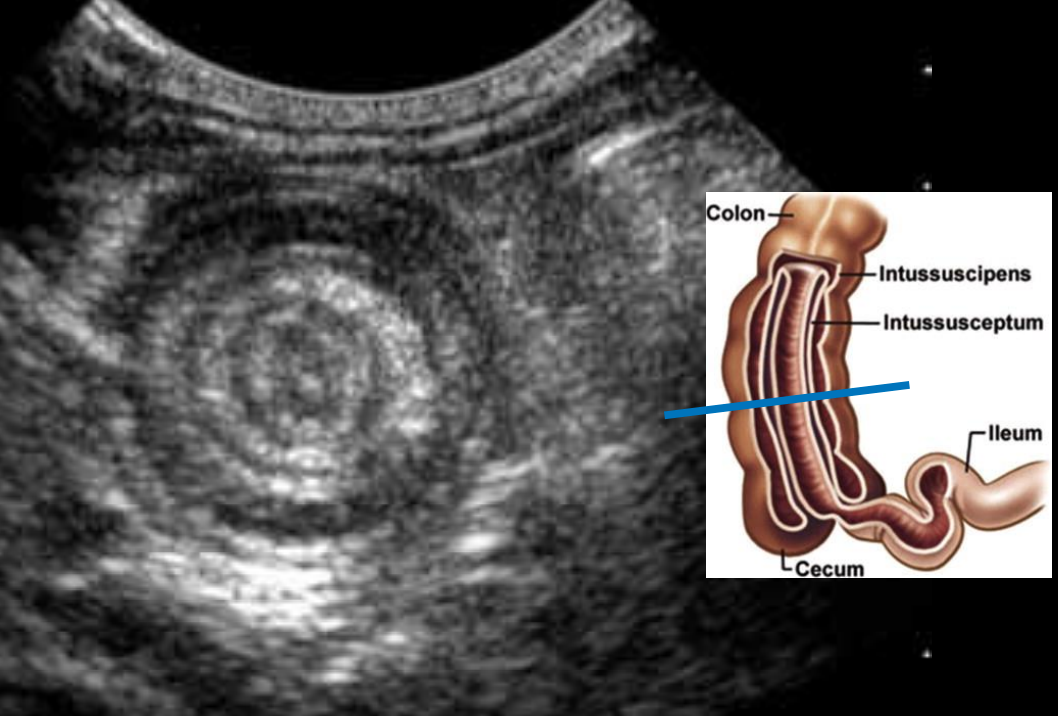

ultrasound

gold standrad investigation

classically shows a ‘target sign’